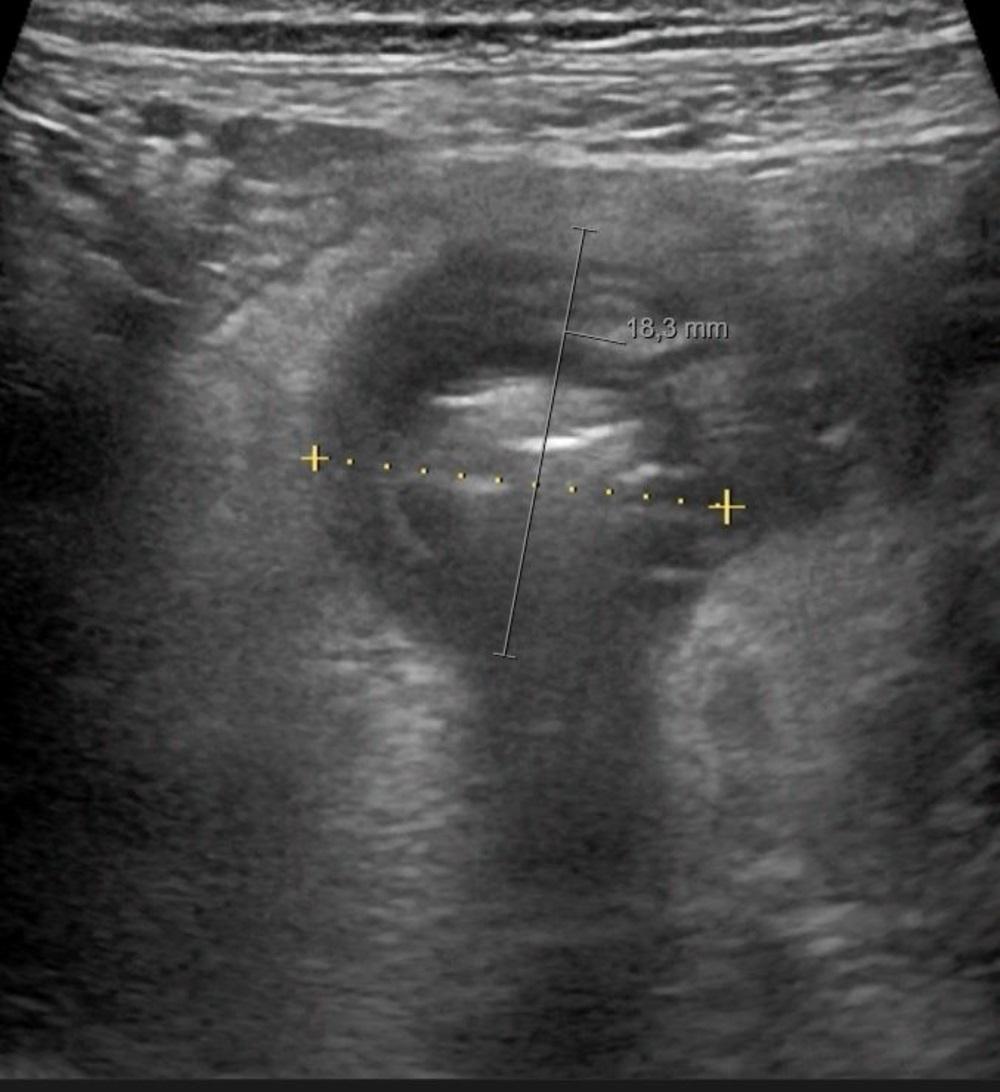

Een 59-jarige vrouw komt naar de SEH met zeurende pijn rechtsonder in de buik sinds 4 dagen. Er is drukpijn op het punt van McBurney, maar geen koorts of misselijkheid. De CRP-waarde is 43 mmol/l. De radioloog verricht echografie.